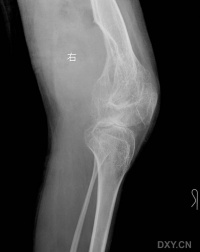

血友病性关节炎

血友病的出血常累及活动较多和承受重力的膝、躁、肘和髓关节,其中以膝关节最为常见。

血友病性关节病的病理改变主要由骨关节反复出血所致。

关节内出血早期引起关节软组织和关节间隙增宽。反复出血者可有含铁血黄素沉积。

中期由于酶的作用使滑膜纤维化透明软骨分解,引起慢性滑膜炎软骨退变和关节表面侵蚀。滑膜增殖引起软骨边缘和软骨下骨侵蚀。软骨的退变与破坏导致关节间隙变窄。关节运动受限可引起废用性骨质疏松

晚期出现软骨下硬化和囊变及关节周围软组织萎缩